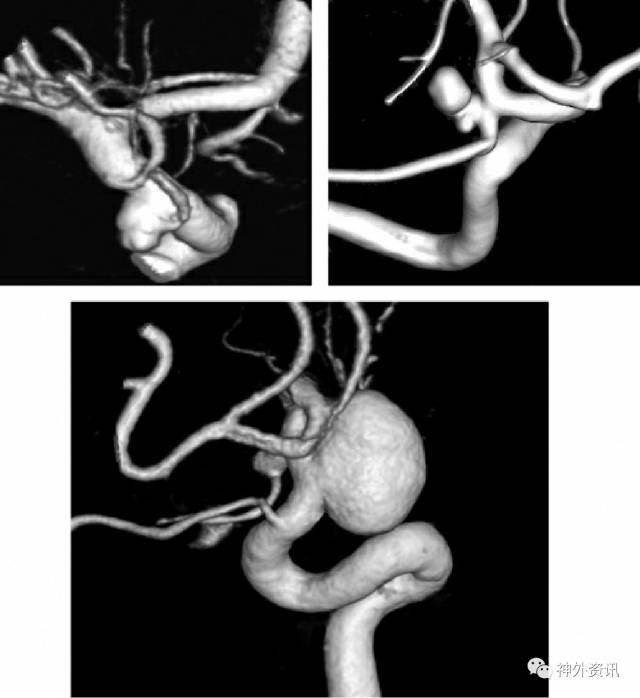

图2:显示起源于颈内动脉(ICA)和PCoA交界处的一个典型PCoA动脉瘤(左上图)。动脉瘤可能偶尔主要源于PCoA(右上图)。大型PCoA动脉瘤可以将ICA融入到他们的瘤颈内(下图)。

PCoA动脉瘤可起源于床突上ICA,靠近PCoA起始部远端(交界部动脉瘤,最常见)或直接起源于PCoA本身(真性PCoA动脉瘤)(参见图2)。大多数PCoA动脉瘤位于PCoA和AChA之间的ICA,融合了两支血管的起始部。PCoA离开ICA后壁后,走行在后内侧,穿过Lilieguist膜,汇入PCA。